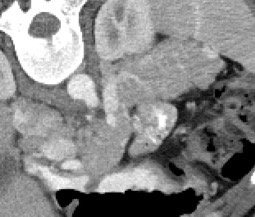

Automated segmentation in medical image analysis is a challenging task that requires a large amount of manually labeled data. However, most existing learning-based approaches usually suffer from limited manually annotated medical data, which poses a major practical problem for accurate and robust medical image segmentation. In addition, most existing semi-supervised approaches are usually not robust compared with the supervised counterparts, and also lack explicit modeling of geometric structure and semantic information, both of which limit the segmentation accuracy. In this work, we present SimCVD, a simple contrastive distillation framework that significantly advances state-of-the-art voxel-wise representation learning. We first describe an unsupervised training strategy, which takes two views of an input volume and predicts their signed distance maps of object boundaries in a contrastive objective, with only two independent dropout as mask. This simple approach works surprisingly well, performing on the same level as previous fully supervised methods with much less labeled data. We hypothesize that dropout can be viewed as a minimal form of data augmentation and makes the network robust to representation collapse. Then, we propose to perform structural distillation by distilling pair-wise similarities. We evaluate SimCVD on two popular datasets: the Left Atrial Segmentation Challenge (LA) and the NIH pancreas CT dataset. The results on the LA dataset demonstrate that, in two types of labeled ratios (i.e., 20% and 10%), SimCVD achieves an average Dice score of 90.85% and 89.03% respectively, a 0.91% and 2.22% improvement compared to previous best results. Our method can be trained in an end-to-end fashion, showing the promise of utilizing SimCVD as a general framework for downstream tasks, such as medical image synthesis and registration.